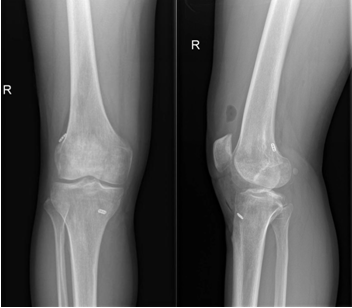

近日,一名31岁男性因打篮球扭伤致“右膝关节疼痛伴行走不稳半年”入院,术前诊断:前交叉韧带部分断裂。考虑患者年轻且有较高的运动恢复需求,在骨科病院刘时璋主任医师的指导下,由冯敏副主任医师主刀完成21点技巧中心

首例关节镜辅助下前交叉韧带损伤“保残+全内”重建术。患者第二日即下地活动,第三天顺利出院。